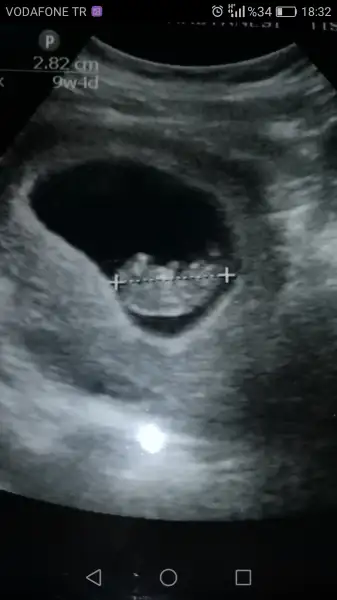

7 haftalık dediğiniz fotoda 6 hafta 4 günlük yazıyor o haftalarda bebeğin yeri sabit olmuyo önemli olan 7 haftadan sonra ne tarafta durduğu diğer fotoda solda yukarda ramzi teorisine göre karından solda olursa bebek erkek oluyo canım çoğu kişide teori tutuyor inşallah bendede tutar

Slm kızlar bugün kont vardı çok şükür herşey yolunda ilk defa hareketlerini gördm miniğimn hıçkırıyo annesi kocaman olmuş dedi Dr nasıl sevndm anlatamam 2hafta snrası ikili içn gün verdi cinsiyet tahminide yaparm dedi hayırlısı inş bklm sizden de fikir istiyorum USG göre :)

• Screenshot_2017-12-22-18-32-31.webp